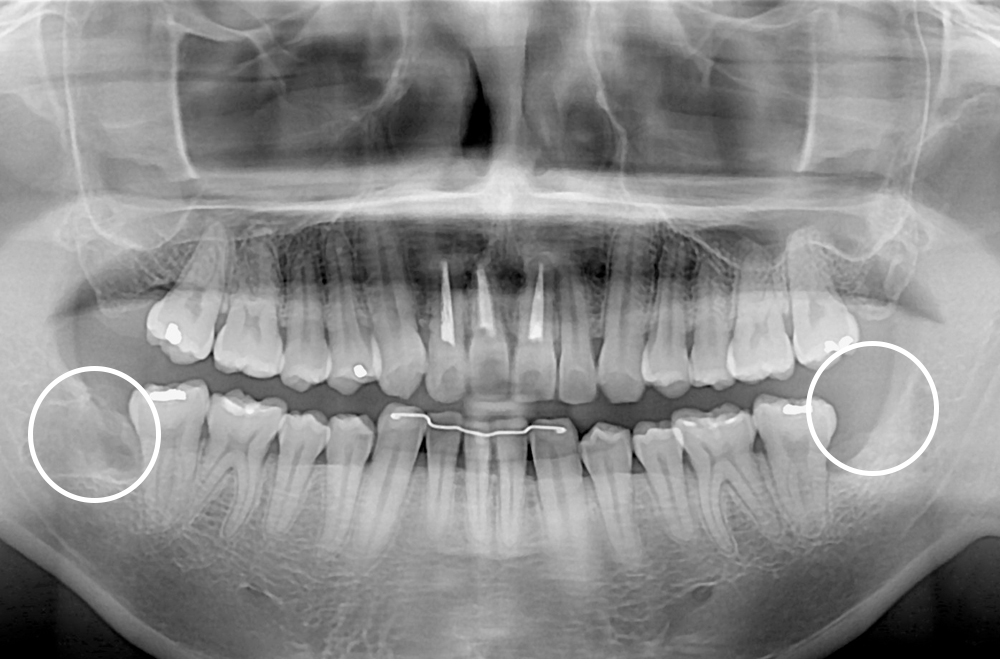

[사랑니] 매복 사랑니 발치

치료전 : 2019-01-09